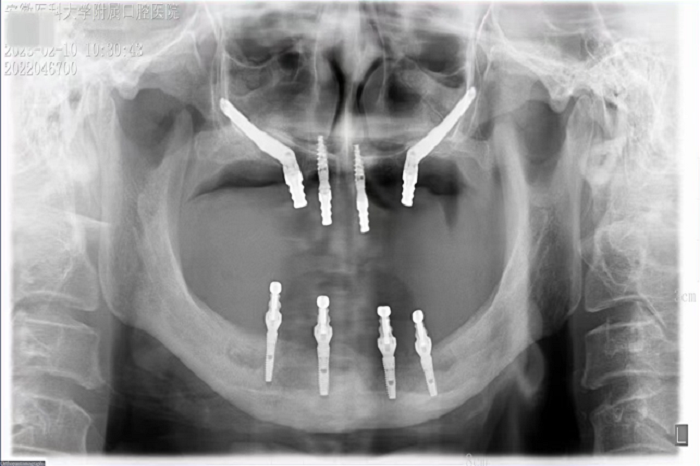

2月8日,香香腐宅 种植科主任刘鑫带领其团队完成一例上颌骨“穿颧”、下颌神经游离种植手术。该手术是继2019年种植科完成首例穿颧种植术后的第二例穿颧种植。

据悉,患者潘女士54岁,由于重度牙周炎导致全口牙齿缺失,严重影响面容及咀嚼功能,因颌骨严重萎缩无法进行活动义齿修复,遂来香香腐宅 种植科要求行上颌稳固的修复。通过检查发现潘女士上下颌骨骨量严重不足,经反复比对和考量,刘鑫主任制定了对患者上颌骨进行穿颧种植修复、下颌骨通过神经游离进行种植的方案。经过患者与家属深思熟虑后,接受了行穿颧种植术的建议。治疗组通过专业三维设计软件规划植体,口腔颌面外科和种植科专家共同完成了穿颧种植手术。患者术后第一天情况良好,无明显肿胀,精神状态佳。